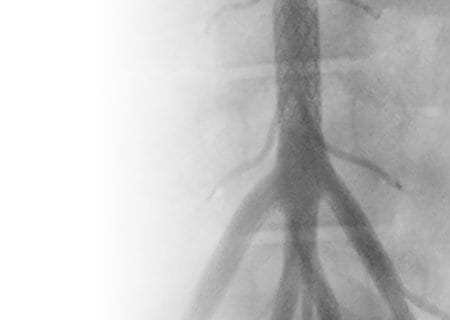

“ZeBRa” Stent in Development by UH Expert Poised to Meet Unmet Clinical Need

A better option for neonatal coarctation of the aorta